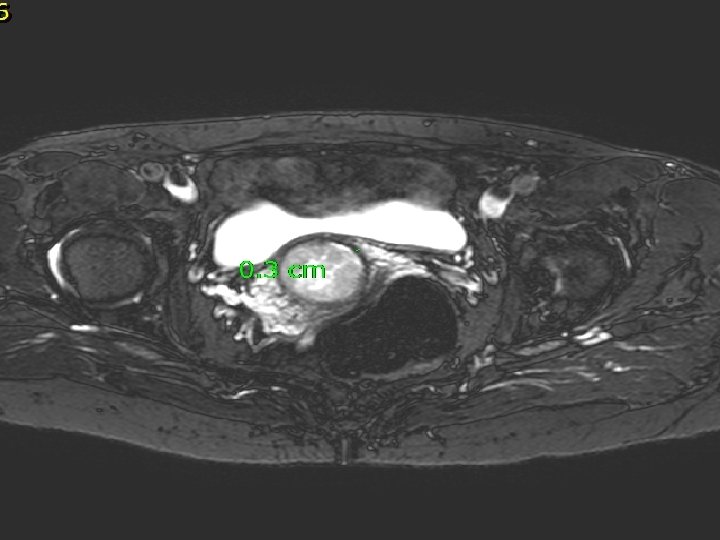

MRI V oblasti cervixu expanzivní útvar 3 cm v průměru s odlišným signálem oproti okolní děloze a vlastním myomům, expanze má vyšší obsah vody. Zaujímá celý vnitřní prostor cervixu, podél expanze zůstává tenký lem tkáně šíře 3 mm. Nikde nepřechází expanze z cervixu na okolní struktury.

Děložní tělo, parametria a poševní manžeta bez nádorové infiltrace Téměř celé děložní hrdlo infiltrované strukturami Karcinosarkomu (M 8990/32), kdy přibližně z poloviny je novotvar tvořen strukturami sarkomovými, z poloviny strukturami méně diferencovaného endometroidního adenokarcinomu. Intaktní tkáň na povrchu cervixu šíře 3 mm. Invaze do krevních ani lymfatických cév nezastižena. Omentum, appendix, pánevní a paraaortální lymfatické uzliny (36) bez maligní infiltrace